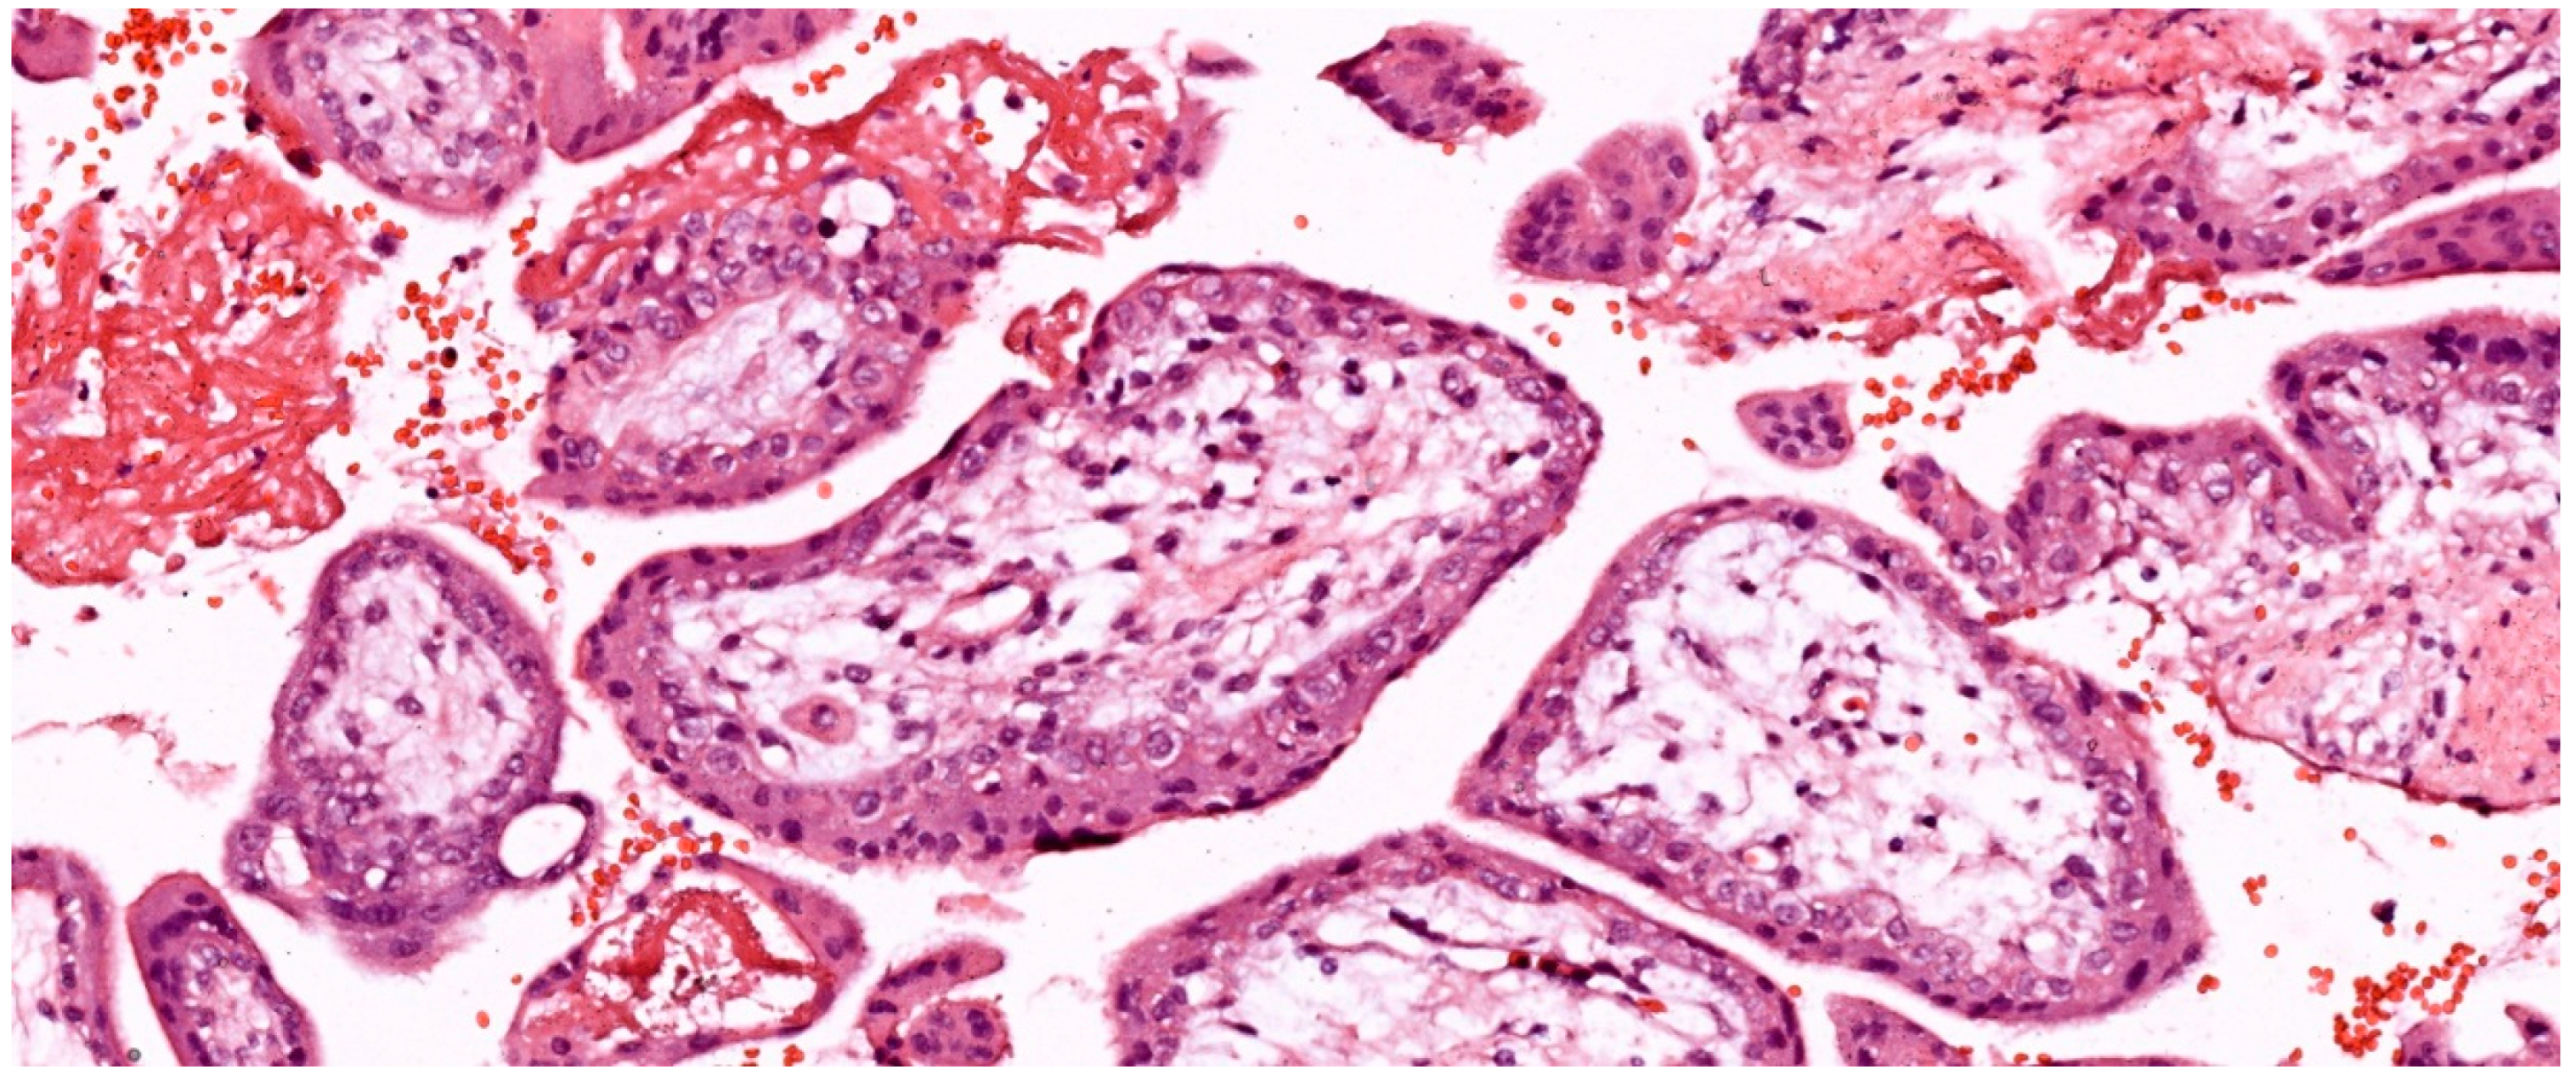

2.3.1. Structure and Development of Chorionic Villi

- Terminal villi: These are connected to stem villi. Terminal villi have a grape-like appearance, characterized by a high degree of capillarization and the presence of highly dilated sinusoids. In the term placenta, terminal villi are smaller, with less stroma, a discontinuous cytotrophoblast cell layer and 4-6 fetal capillaries in cross-section. In terminal villi, fetal capillary vessels and syncytiotrophoblast are separated only by a thin basement membrane, making these villi the most suitable site for maternal-fetal exchange. In the mature placenta, terminal villi represent 40% of the total villous volume of the placenta. Due to their small diameters, the sum of their surfaces represents 50% of the total villous surface area [58]. Terminal villi are considered the functional unit of the placenta. The transfer of electrolytes, O2, CO2 and nutrients between mother and fetus occurs at this level [6].